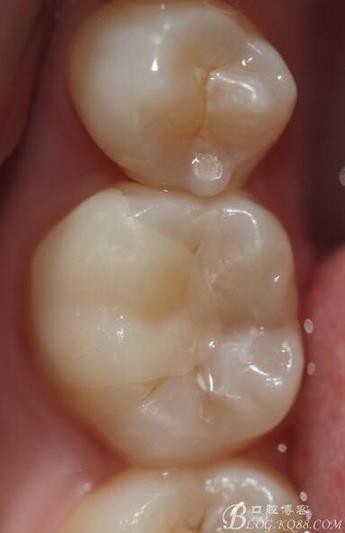

主訴:雙側(cè)下后牙疼痛一月余

病史:近一個(gè)月雙側(cè)下后牙疼痛,自發(fā)性 陣發(fā)性鈍痛,進(jìn)食嵌塞加重,求診

查:雙側(cè)下6頰HE面齲壞 探診疼痛 冷熱刺激 遲反應(yīng)疼痛 叩診(-)頰側(cè)齲壞平齦

X線(xiàn):雙側(cè)下6 齲壞已接近髓腔

診斷:雙側(cè)下6 慢性牙髓炎

治療方案:雙側(cè)RCT+CAD-CAM

這里我單做右側(cè)的詳細(xì)步驟